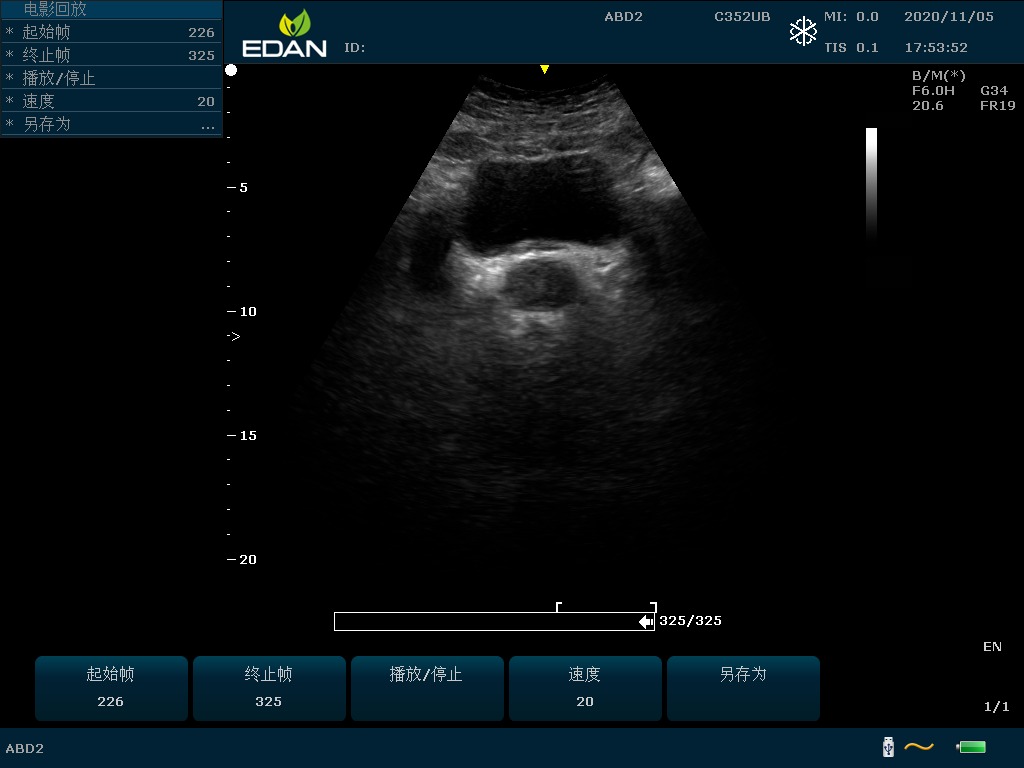

Особенность U60 Edan — расширенное применение. Ультразвуковой аппарат рекомендован для абдоминальных исследований, гинекологии и акушерства, кардиологии, педиатрии, урологии, изучения малых органов, сосудов. Для U60 Edan используются конвексные, линейные, фазированные и внутриполостные датчики.

Передовые технологии позволяют повысить качество визуализации в несколько раз. УЗИ-аппарат U60 Edan отличается возможностью быстрой настройки визуализации. Специальные функции позволяют моментально отображать данные за счет быстрой оптимизации параметров. Режимы визуализации: B-mode, M-mode, Color Doppler, Power Doppler Imaging, Pulsed Wave Doppler, Continuous Doppler.